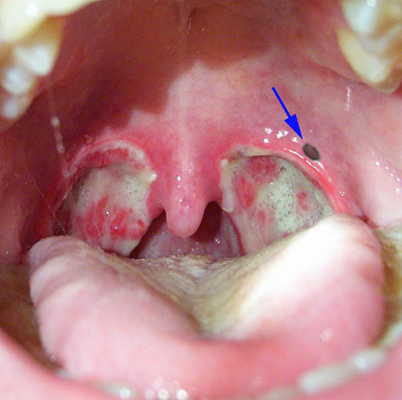

扁桃體週膿腫圖片

A:扁桃體周膿腫一旦形成,要膿腫切開引流,加抗炎治療。首先要用注射器穿刺膿腔,抽出膿液,確診膿腫形成。在穿刺點周圍黏膜局麻,用手術刀切開粘膜肌肉,進入膿腔,會有膿液湧出,用大的止血鉗,插入膿腔,擴大膿腔切口,使更多的膿液流出來,同時用注射器,鹽……